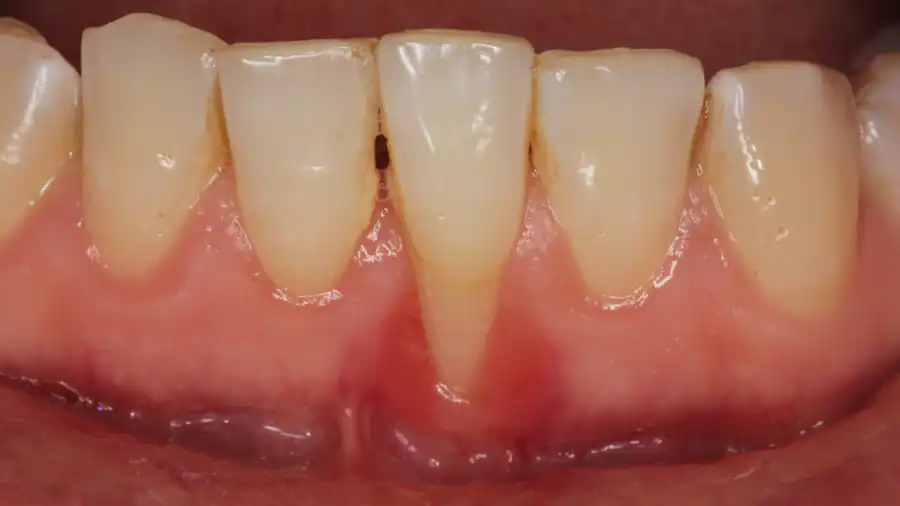

Dấu hiệu nhận biết viêm cận răng đó là thường bị mảng vụn thức ăn tích tụ nhiều tại các khoảng trống giữa lợi và răng.

Viêm lợi lúc này nếu không được điều trị, chăm sóc đúng cách sẽ khiến đẩy lùi ra phía sau lớp lợi và xương hàm ở phía trong cùng. Từ đó khu vực quanh răng tạo nên những lỗ hổng.

Viêm lợi cận răng

Giữa lợi và răng, các khoảng trống dễ gây nhiễm khuẩn do thường xuyên bị nhiều mảng vụn thức ăn tích tụ. Khi ở dưới vòm lợi tích tụ nhiều bựa răng sẽ làm cơ thể phải nỗ lực chiến đấu với vi khuẩn.

Trong cơ thể, những độc tố, chất enzyme tích tụ sẽ khiến phá hủy mô liên kết, hàm. Lợi lúc này sẽ viêm nhiễm, sưng đỏ, đau nhức, chảy máu, sưng má, hơi thở có mùi hôi, …